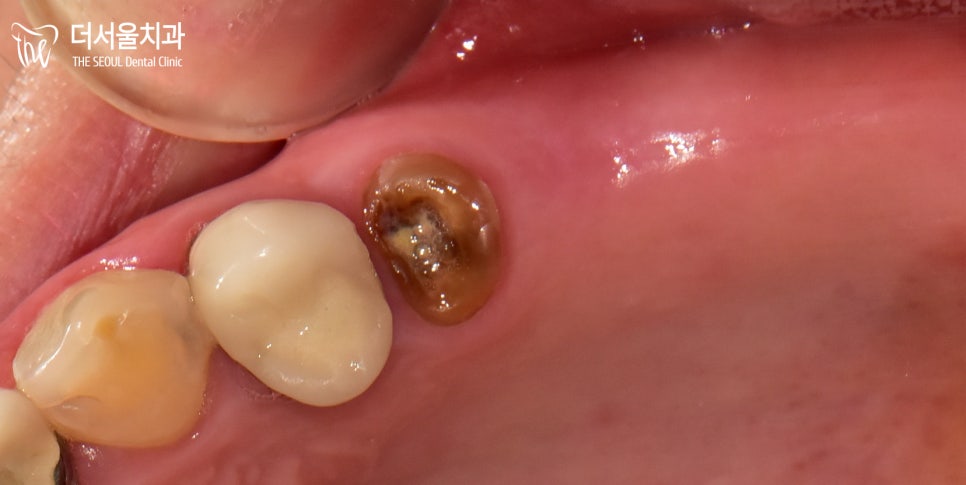

자~ 우선 본격적인 식립에 앞서

구강 검진을 진행했습니다.

좌측 어금니가 빠진 채로 남아 있었으며

소구치 하나는 잔존 치근만 남아있는 모습이네요.

이렇게 한쪽 치아들이 빠진 채로 생활을 하면

편측 저작 습관이 자연스레 생길 수밖에 없습니다.

방치를 하게 되면 치조골 소실이 나타날 수밖에 없고요.